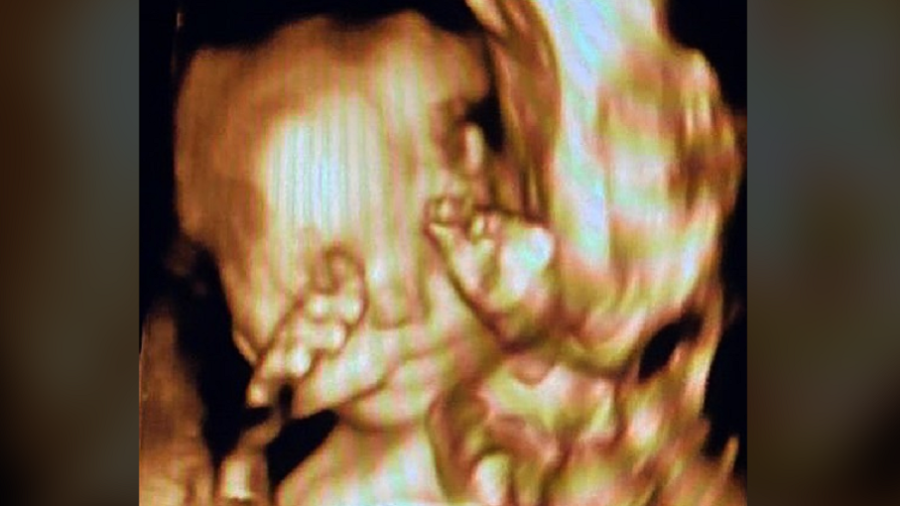

PRIMEIRA FILHA Eduardo Bolsonaro brinca que filha faz ‘sinal de arminha’ em ultrassom O deputado federal Eduardo Bolsonaro (PSL-SP) postou uma foto hoje do ultrassom da sua primeira… há 5 anos